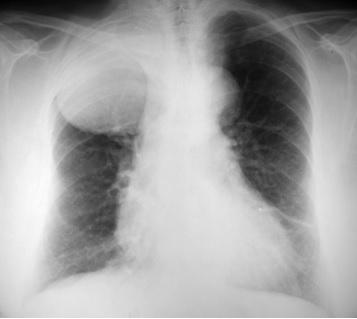

Ayer tuvimos una video-conferencia con un Hospital de Alabama. Suelen hacerlo una vez al mes y consiste en que cada servicio se comenta un caso y los médicos del otro hospital tienen que hacer un diagnóstico diferencial e intentar averiguar el diagnóstico. Para ayudar al diagnóstico muestran imágenes de lesiones o de anatomía patológica, en el caso de que lo necesiten. Fue muy interesante y además sirve para practicar inglés.